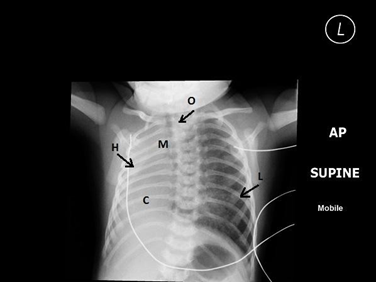

Figure 1.1 Chest X-ray.

H: completely opaque Rt. hemi thorax, M: ipsilateral mediastinal shift, C: apparent dextrocardia, L: hyperinflation of contra lateral lung, O: coiled NG tube